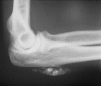

Algunas enfermedades del tejido conectivo pueden asociarse a calcificación distrófica, especialmente la esclerodermia y la dermatomiositis (26, 27). En la primera, la calcificación es habitualmente de pequeña cuantía y aparece usualmente en la piel y tejido celular subcutáneo de las manos; en el síndrome CREST la calcinosis es un rasgo fundamental para su diagnóstico e inicia el acrónimo, con lesiones de aparición insidiosa localizadas principalmente en las extremidades superiores (28) y en especial en los dedos de las manos (Fig. 2), las que pueden ulcerarse y dar salida a un material grumoso calcáreo. Los depósitos de calcio se presentan como nódulos de 1 mm a 2 cm de diámetro o como microdepósitos en la dermis normal en forma de microcristales perifibrilares o cristales en forma de aguja (29). Su aspecto radiológico es característico (Fig. 3), por lo que raramente se biopsian (30) (Fig. 4).

FIG. 3.--Aspecto radiológico del síndrome CREST.